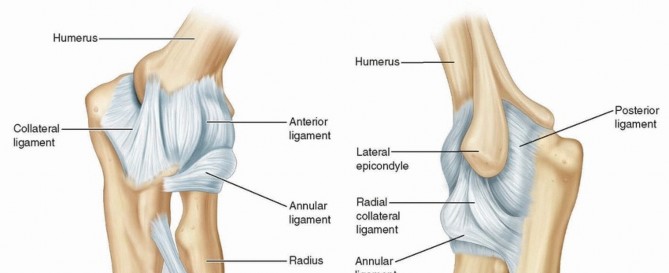

Chapter 40 Arthroscopic Treatment of Elbow Loss of Motion Laith M. Al-Shihabi Chris Mellano Robert W. Wysocki…